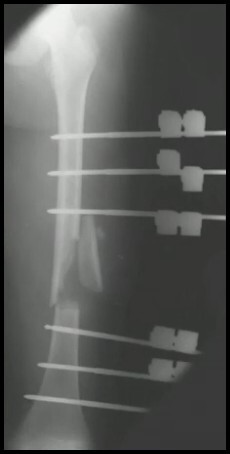

7

Q

FX Diafisária do Fêmur

TTO 6 - 10 anos?

A

HASTES FLEXÍVEIS

ou

Placa (>50 Kg)

Fixador Externo (Cominuição)